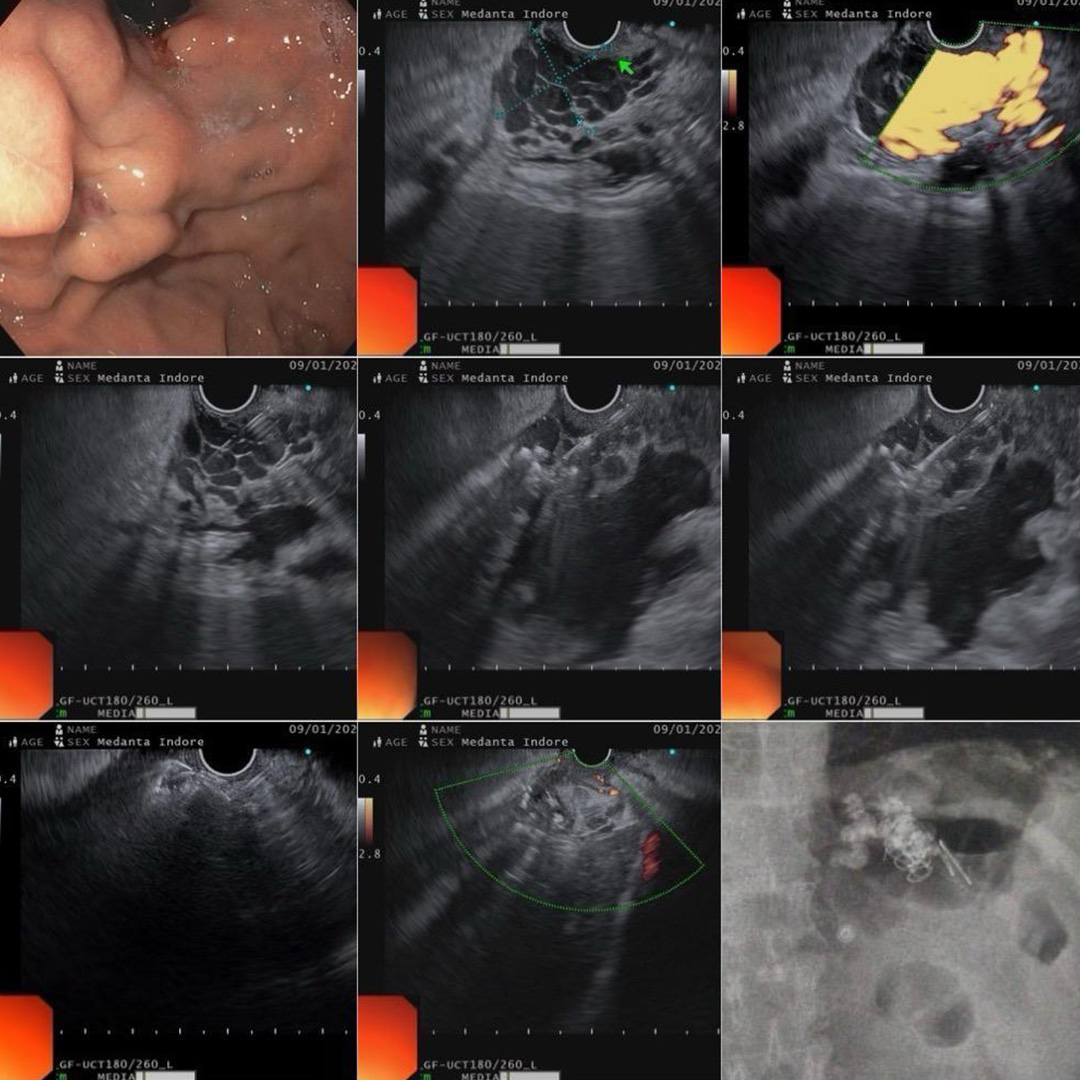

EUS coil & glue injection

70 yr male came with massive gastric variceal bleed. History of glue injection in 2021 elsewhere. We did EUS coil & glue injection. 3 large coils & 2 ml of glue + lipoidal. Completely obliteration of flow in varix achieved immediately.